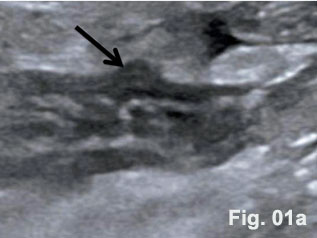

A 34-year-old complained about a sudden onset of right-lower-quadrant pain. Preoperative ultrasound revealed the appendix with a hypoechoic and thickened wall and the so-called dome sign [Figure 1]. Abdominal tenderness and other clinical signs were suggestive of acute appendicitis. On clinical examination tachycardia (108/min), febrile temperature (38.60 C) and dehydration were documented. Blood test results showed leucocytosis (13,2/nl). Emergency laparoscopic appendecectomy was performed. A large inflammatory mass was found involving the appendix [Figure 2]. The histological specimen revealed the combined presentation of congenital and acquired diverticula. Histopathological examination confirmed phlegmonous inflammation of the appendix and periappendicitis caused by inflammation of diverticula [Figure 3].

Here we present the sonographic findings of a diverticulitis of the appendix including histology. The diverticulum could be clearly displayed in an otherwise thickened appendix with well preserved layers. Diverticula of the appendix can be true or congenital or false (due to acquired mechanisms) [Table 1 and 2] [(1)]. The wall of congenital diverticula contains all the normal histological components of the appendiceal wall. The walls of the acquired or false appendiceal diverticulum are only composed of mucosa, some loose areolar tissue and the serosa. This group either develops during the growth of the fetus or before inflammatory changes make there appearence in the appendix. The prevalence of congenital diverticula found in appendicectomy specimens range from 0,004 % to 0,6 % [(2)]. Diverticulitis of diverticula of the appendix is even rarer. Approximately 78% of cases were associated with varying signs and degrees of inflammation at time of their removal [(3)]. Perforation was observed in 66 % of cases with a high mortality (30-fold compared with acute appendicitis). Four subtypes of appendicular diverticulosis have been described in the literature [Table 2] [(1)]. The majority of diverticula of the appendix described in the literature were incidental findings observed during routine X ray examination of the gastrointestinal tract. While it is agreed that many people with appendiceal diverticula live healthy, normal lives, there can be no doubt that with the onset of complications, life is threatened by inflammation and complications.